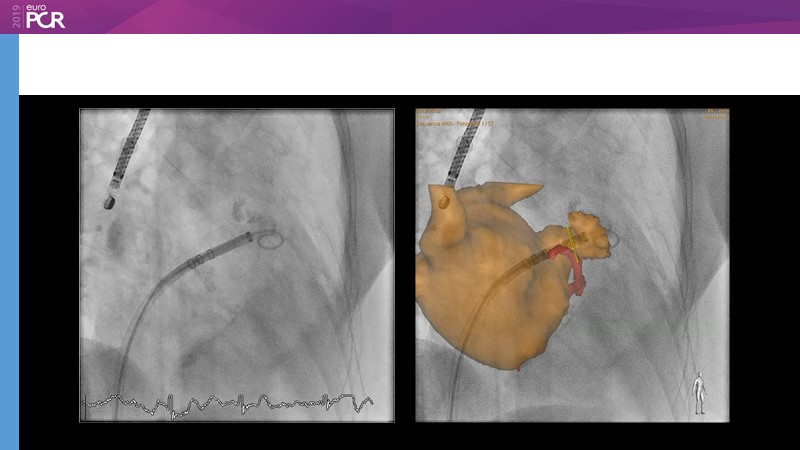

I. Cruz-Gonzalez

Pre-procedure planning

M. Sandri

Optimising procedural outcome and safety